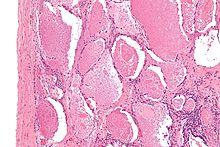

Micrograph of pulmonary alveolar proteinosis, showing the characteristic airspace filling with focally dense globs referred to as chatter or dense bodies. H&E stain.

Lung washings or tissue for histopathologic analysis are most commonly obtained using bronchoalveolar lavage and/or lung biopsy.[12] Characteristic biopsy findings show filling of the alveoli (and sometimes terminal bronchioles) with an amorphous eosinophilic material, which stains strongly positive on PAS stain and the PAS diastase stain. The surrounding alveoli and pulmonary interstitium remain relatively normal.[13] Electron microscopy of the sample, although not typically performed due to impracticality, shows lamellated bodies representing surfactant.[14] An alternative diagnosis with similar histomorphologic findings is Pneumocystis jirovicii pneumonia.[14]

Lung washings characteristically yield a fluid which is "milky"composition. Under the microscope, samples show 20-50 micrometer PAS-positive globules on a background of finely granular or amorphous PAS-positive material. There is typically a low numbers of macrophages and inflammatory cells (although this is variable).[13][14]